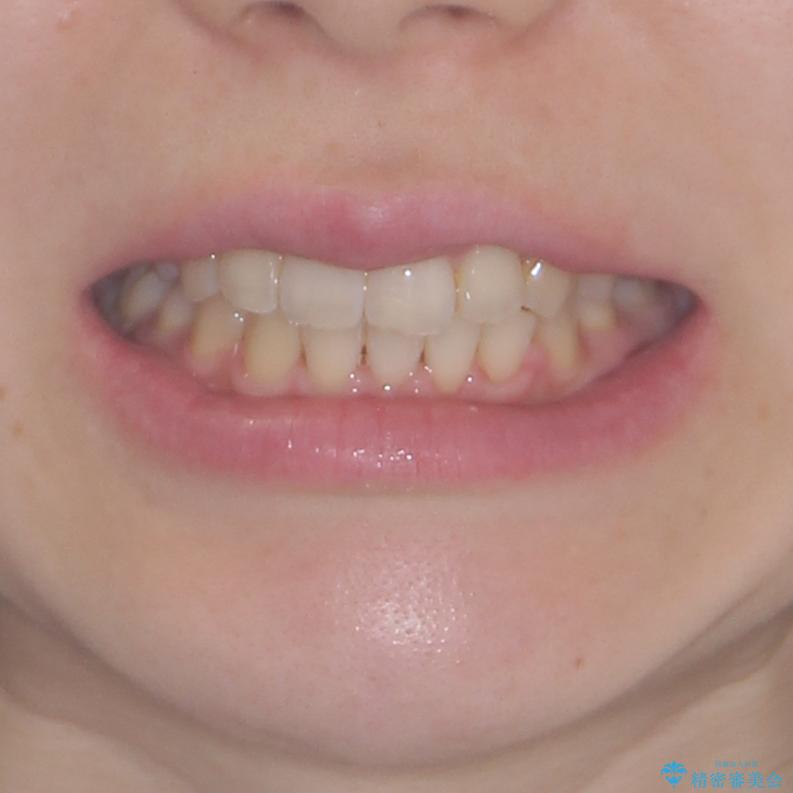

- 右上の八重歯と、左下八重歯を抜いてしまったことを気にして来院された患者様です。

下顎は既に犬歯を1本抜歯しているため、上顎右側第一小臼歯を抜歯し、ワイヤー装置にて歯列を整えることとしました。

変則的な抜歯となるため、正中と人中がずれる可能性がありましたが、仕上がりは上下正中を揃えることができました。